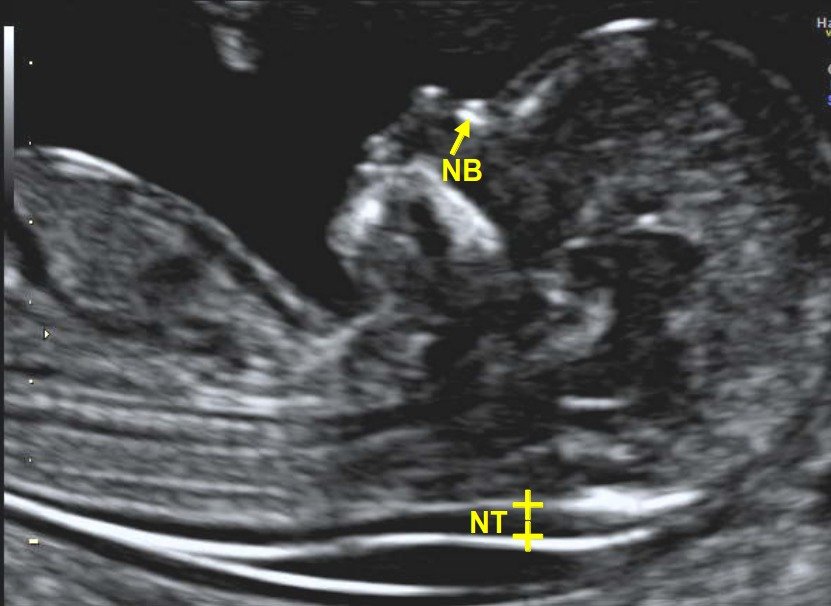

An NT (Nuchal Translucency) scan is a prenatal ultrasound screening done to detect chromosomal abnormalities such as Down syndrome in a fetus. The NB (Nasal Bone) test is an integral part of this screening.

During the scan, doctors measure the fluid-filled space behind the fetus’s neck (nuchal translucency or nuchal fold) and assess its thickness. The test also checks whether the fetus has developed a nasal bone.